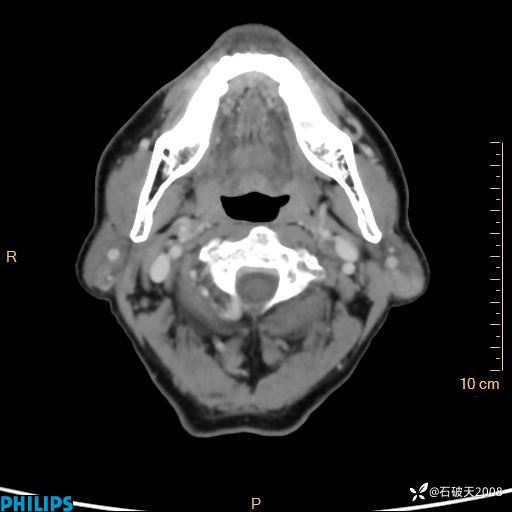

病例分享:老年男性,颈部占位,一周后公布病理

胡志勇HZY 达人已点赞男 61岁 主 诉:发现左侧面部肿物1年余。

现病史:患者于1年余前无意间发现左侧耳下有一肿物,大小如“花生米样”,无压痛,无明显红肿,无畏寒、发热,无咳嗽、咳痰,无盗汗、心慌,无手足颤动、胸闷及性格改变,未在意,未给予特殊处理,2天前至我院行彩超示: 左侧腮腺内低回声(考虑肿大淋巴结),现患者为求进一步诊治,遂来我院就诊,门诊以“局部肿物”为诊断收住我科。自发病来,患者神志清,精神可,饮食睡眠尚可,大小便正常,近期体重无下降。

冠状位